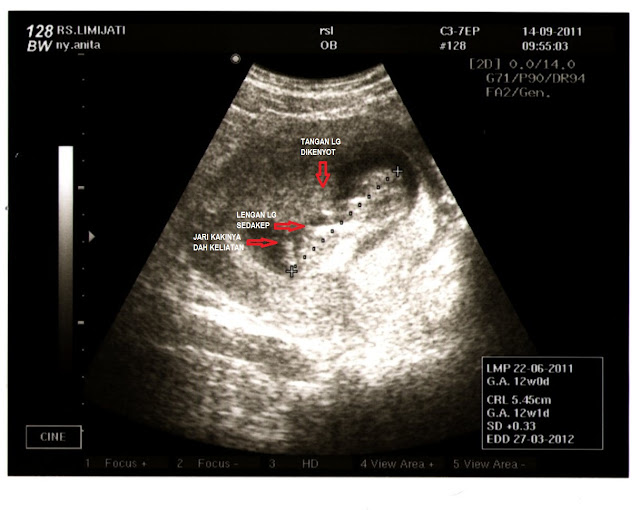

Hasil USG alhamdulillah si dedek lincah, lumayan aktif bergerak-gerak, badannya, lengan dan kakinya gerak-gerak semua. Lagi renang gaya punggung yah dek...hihihi....tapi kok sambil ngenyot jempol sich...lucunya si dedek. Bentuk tubuhnya sudah mulai kelihatan lengkap, jari-jarinya juga mulai kelihatan terbentuk. Tadi sama dokter ditunjukkan bagian-bagian tubuhnya. Kata dokter emang badan si dedek sekarang belum proporsional. Proporsi kepala dan badannya cuma beda dikit... hehehe... sekarang dedek dari kepala sampai bokong dah sepanjang 5,54 cm. Sesuai dengan usia kehamilan, malah seperti biasa, lebih sehari dari usia berdasarkan LMP jadi 12 minggu 1 hari. Dari gambarnya kok keliatan mulai sempit ya kantung amnionnya? Kasihan si dedek jadi kurang bebas bergerak.

| Si Dedek usia kehamilan 12 minggu |